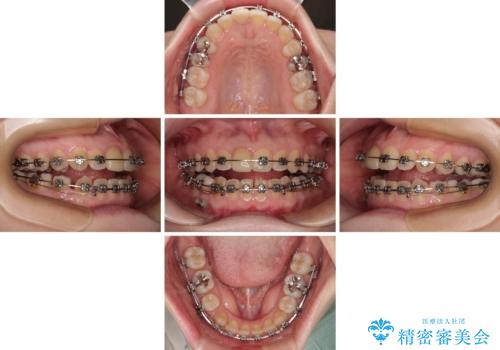

- 矯正装置

- メタルブラケット

- 治療期間

- 1年5ヶ月